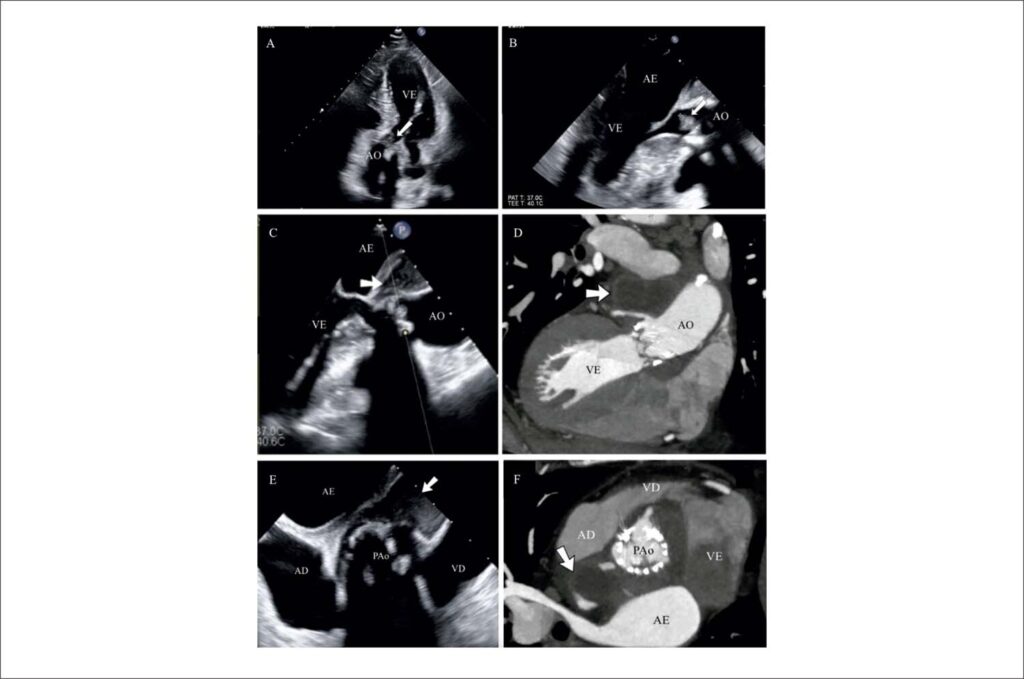

Endocardite de Prótese Valvar Aórtica com Abscesso Paraórtico Extenso: A Relevância da Multimodalidade de Imagem